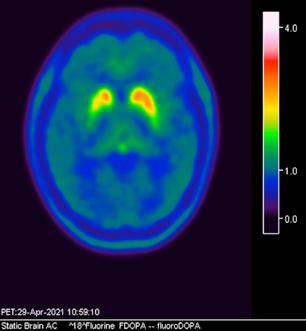

CASO CLÍNICO

axial fusionada de PET-RM 3T con

con disminución de la captación del radiotrazador a nivel de ambos putámenes en la región posterior y media de predominio derecho así como disminución en el caudado ipsilateral.

2. Reconstrucción tridimensional avanzada de imagen híbrida PET-RM 3T con 6-[18F]FDOPA observando disminución de la captación del radiotrazador a nivel de ambos putámenes en la región posterior y media así como en el núcleo caudado derecho.

Figura 1. Imagen

6-[18F]FDOPA

Figura 3. Reconstrucción mediante imagen molecular de imagen híbrida PET-RM 3T con 6-[18F] FDOPA observando disminución de la captación del radiotrazador a nivel de ambos putámenes en la región posterior, media y anterior así como en ambos núcleos ca dados de predominio derecho.

Figura 4. Reconstrucción mediante imagen molecular de imagen híbrida PET-RM 3T con 6-[18F]FDOPA observando captación adecuada y conservada del radiotrazador en el cuerpo estriado (ambos putámenes y núcleos caudados) en un paciente negativo para enfermedad de parkinson.

En cuanto al campo de los estudios de imagen convencional y de laboratorio no existe alguna prueba que pueda confirmar la enfermedad. Sin embargo, las imágenes de diagnóstico por métodos de imagen molecular del tipo no invasivas, como la tomografía por emisión de positrones (PET) en conjunto con un resonador de 3 tesla (RM 3T), pueden respaldar el diagnóstico de un médico, actualmente éste método tiene una sensibilidad diagnóstica de 95.4%, especificidad 100%, valor predictivo positivo del 100% y valor predictivo negativo del 87.5%. (5,6)

La enfermedad de parkinson es una enfermedad neurodegenerativa con afectación principalmente motora (temblor, rigidez y acinesia) de sospecha y diagnóstico clínico, ante la limitación de los estudios de laboratorio y métodos de imagen convencional para el diagnóstico toman gran relevancia las técnicas de imagen molecular no invasivas como el PET-RM y PET-CT con 6-[18F]FDOPA que cuentan con gran sensibilidad y especificidad para respaldar o descartar el diagnóstico médico ante la sospecha de la enfermedad de parkinson y algunas otras enfermedades del trastorno del movimiento.